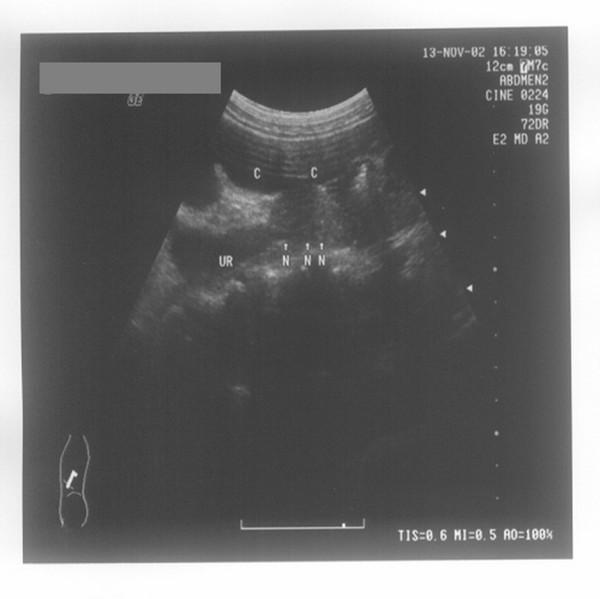

Conventional transabdominal ultrasound usually fails to visualize parts of the ureter or extrahepatic bile duct covered by bowel gas. In this study, we propose a new method for gaining acoustic access to the ureters and extrahepatic bile duct to help determine the nature of obstruction to these structures when conventional transabdominal ultrasound fails.

The normal saline retention enema method, that is, using normal saline-filled colons to gain acoustic access to the bilateral ureters and extrahepatic bile duct and detecting the lesions with transabdominal ultrasonic diagnostic apparatus, was applied to 777 patients with obstructive lesions, including 603 with hydroureter and 174 with dilated common bile duct, which were not visualized by conventional ultrasonography. The follow-up data of all the patients were collected to verify the results obtained by this method.

Of the 755 patients who successfully finished the examination after normal saline retention enema (the success rate of the enema is about 98%), the nature of obstruction in 718 patients was determined (the visualizing rate is approximately 95%), including 533 with ureteral calculus, 23 with ureteral stricture, 129 with extrahepatic bile duct calculus, and 33 with common bile duct tumor.

Colons filled fully with normal saline can surely give acoustic access to the bilateral ureters and extrahepatic bile duct so as to determine the nature of obstruction of these structures when conventional transabdominal ultrasound fails.